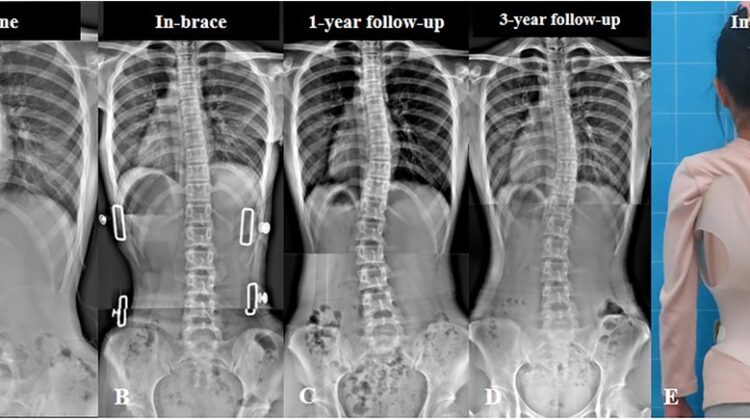

شارك في الدراسة 135 مراهقًا يعانون من جنف بسيط إلى متوسط، وكان لديهم انحناء أساسي للعمود الفقري بين 20° و40°. جميع المشاركين ارتدوا حزامًا طبيًا مخصصًا للظهر والصدر لمدة لا تقل عن سنة، وتمت متابعتهم حتى اكتمال نمو العظام لديهم.

قبل العلاج، كان متوسط الانحناء الأساسي للعمود الفقري في المجموعة الأولى 30.6°، وفي المجموعة الثانية 31.7°.

أثناء ارتداء الحزام، انخفض الانحناء إلى 22.9° و24.2° على التوالي.

المراهقين غير المكتمل نمو عظامهم يحتاجون أن يكون الانحناء داخل الحزام أقل من 25°، أما المكتملون فالأفضل أن يكون أقل من 30°.